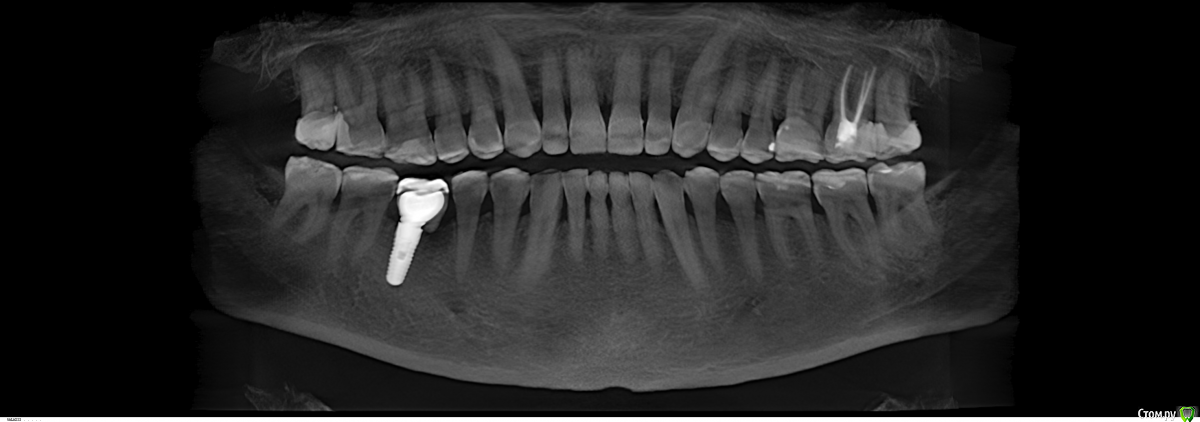

Robinbobin Опубликовано 27 марта, 2015 Поделиться Опубликовано 27 марта, 2015 (изменено) Пациент 57 лет с жалобами на стираемость зубов,чувствительность и бруксизм Хотелось бы услышать ваше мнение!!!! Изменено 27 марта, 2015 пользователем Robinbobin Ссылка на комментарий

Евгений Ходыкин Опубликовано 27 марта, 2015 Поделиться Опубликовано 27 марта, 2015 1) Стабилизировать пародонт.2) Закрытие рецессий, где это возможно.3) Вакс + мокап.4) Временный тотал.5) Постоянный тотал. 1 Ссылка на комментарий

SDC Опубликовано 27 марта, 2015 Поделиться Опубликовано 27 марта, 2015 (изменено) в планах сделать керамические жевательные и режущие края зубовА я бы в 57-летнем возрасте настаивал на комбинированных, с золотой окклюзионной поверхностью коронках с кольцевой гирляндой на все моляры и безметалл на топ 20.удаление 8-х http://s020.radikal.ru/i712/1503/33/4e3a55681950.jpg http://s003.radikal.ru/i204/1503/2b/6265c6920c6f.jpg Изменено 27 марта, 2015 пользователем SDC Ссылка на комментарий